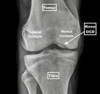

Review mediolateral dog stifle joint anatomy.

Review craniocaudal dog stifle joint anatomy.